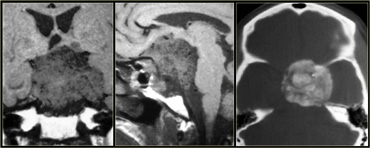

Skull base

Common skull base tumors are listed in the table on the left.

These tumors either arise from extracranial structures like the sinuses (sinonasal carcinoma), or from the skull base itself (chordoma, chondrosarcoma, fibrous dysplasia).

Chordoma is usually located in the midline, while chondrasarcoma usually arises off the midline.

On the left a midline tumor arising from the clivus.

This is the typical presentation of a chordoma.

The differential diagnosis would include a metastasis and a chondrosarcoma.

On the left another skull base tumor located off midline.

This is a typical presentation for a chondrosarcoma.

The differential diagnosis would include a metastasis and a paraganglioma.

Chondrosarcomas can be located in the midline and chordomas are sometimes located off midline but those cases are exceptional.